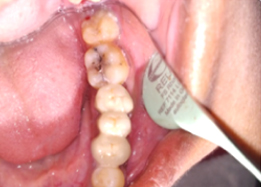

PRE OP Clinical Photograph Measuring Probing Depth